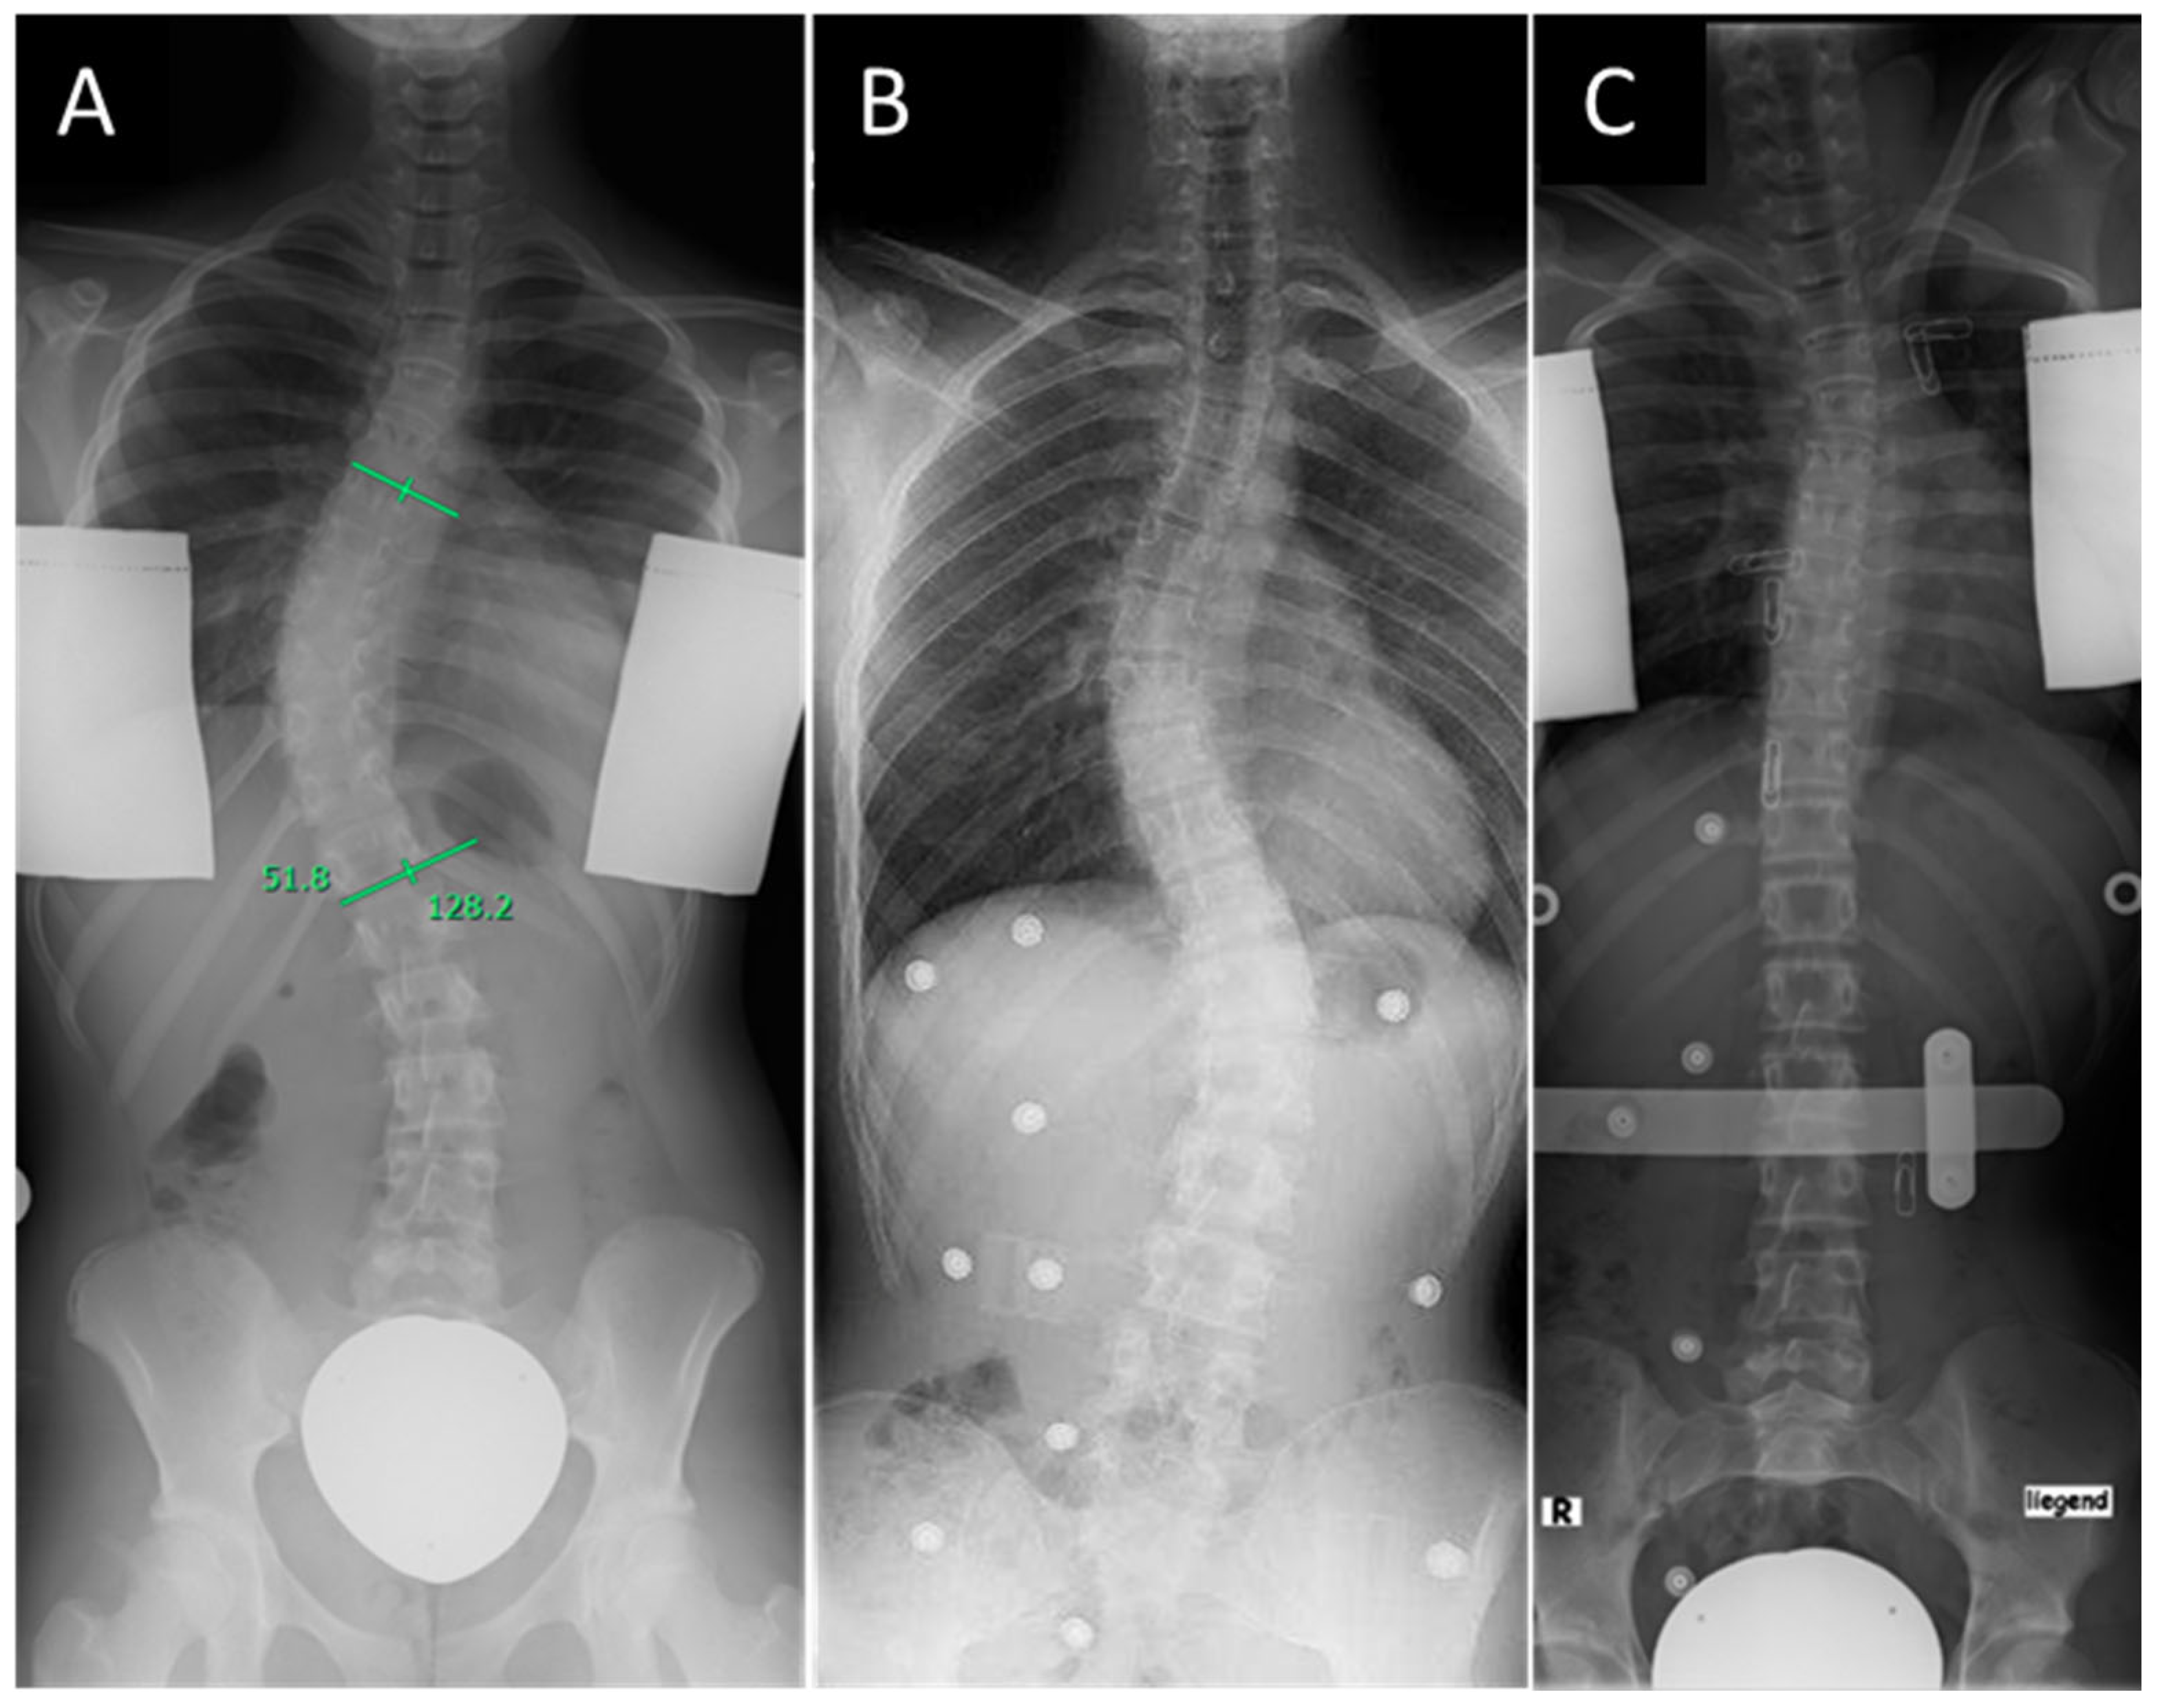

Figure 1.

Right thoracic idiopathic scoliosis of Lenke type 1 identified in a standing radiograph (A), standing radiograph to assess the correction of the curve in the Chêneau corset (B), and supine radiograph to assess the correction of the curve in the Charleston Bending Brace (C).

It is the best alternative to traditional all-night bracing therapy [26,27,28,29,30]. Overcorrection in the night orthosis is achieved through maximum lateral rotation in the direction opposite to the curvature, with simultaneous pressure on the apex of the curvature and an axillary abutment [15]. In the supine position, the spine is 5–7 cm longer and therefore allows for a larger correction area, which is of particular importance when utilizing the axillary abutment. Furthermore, the physiological shape of the spine is flattened in the supine position. This results in an enhanced ability to correct the major and minor curves (Figure 1) [31]. However, there is still an ongoing discussion regarding the superiority or non-inferiority of the Charleston Bending Brace compared to custom-made full-time braces such as the Chêneau brace. Several systematic reviews evaluated the available studies which compared the outcomes after treatment with nighttime or full-time braces [31,32,33]. Due to the retrospective nature of the majority of the studies, the evidence level was low, and no clear treatment recommendations emerged from the studies. The comparability of the studies is complicated not only by different methodical approaches and defined endpoints but also by the wide variety of patient factors that can influence the outcome. Therefore, it is important to assess which patient factors influence initial correction as well as medium-term outcomes.